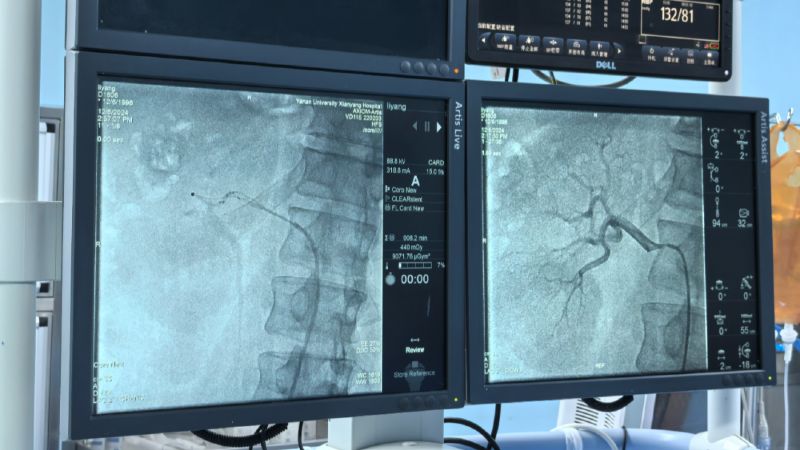

術(shù)中通過(guò)對(duì)左右腎動(dòng)脈造影,了解腎動(dòng)脈解剖結(jié)構(gòu)、評(píng)估腎臟灌注情況。而后順利將射頻消融導(dǎo)管的電極頭推至腎動(dòng)脈主干及分支中遠(yuǎn)段,雙側(cè)腎動(dòng)脈累計(jì)消融16次,涵蓋相應(yīng)分支及主干,共完成78個(gè)有效消融點(diǎn),完成后再次行雙腎動(dòng)脈造影,評(píng)價(jià)手術(shù)對(duì)腎動(dòng)脈形態(tài)和腎血流影響,累計(jì)用時(shí)僅60分鐘高效圓滿完成。術(shù)前血壓由154/110mmHg,手術(shù)完成后血壓130/94mmHg,即刻血壓下降效應(yīng)明顯,直至目前術(shù)后減少三種降壓藥物,監(jiān)測(cè)血壓維持在120/70mmHg左右,手術(shù)效果理想,長(zhǎng)期血壓下降情況我們將持續(xù)隨訪關(guān)注。